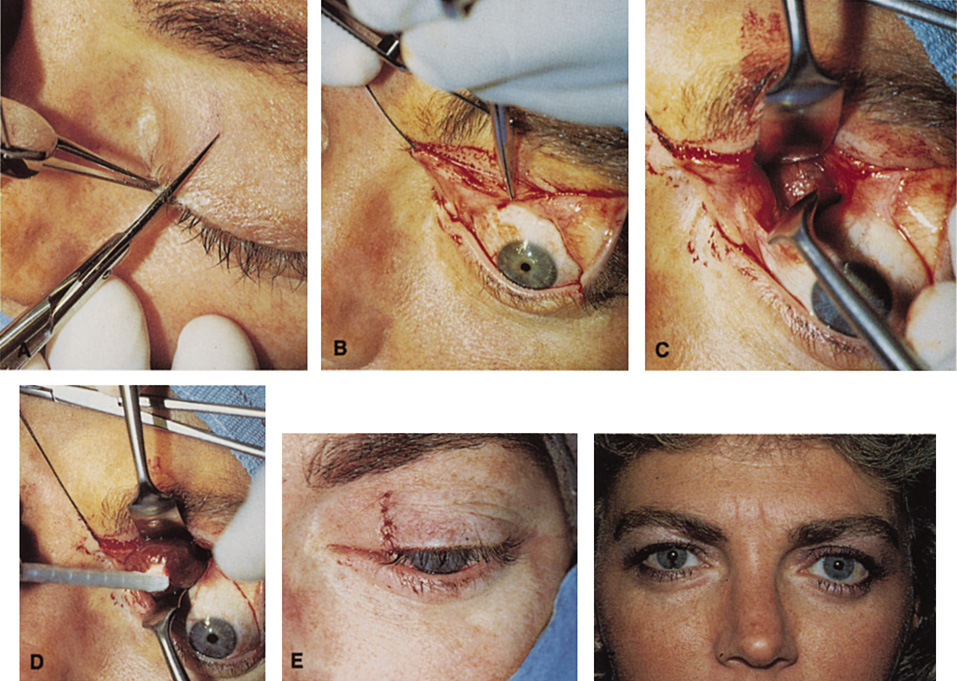

Fig. 12. A. The lateral canthotomy incision is reapproximated with simple closure

of the superior and inferior crura of the lateral canthal tendon. A drain

from the temporal fossa has been brought out through a separate stab

incision posteriorly. 12B. Excellent postoperative scar camouflage is obtained by this approach.

Fig. 12. A. The lateral canthotomy incision is reapproximated with simple closure

of the superior and inferior crura of the lateral canthal tendon. A drain

from the temporal fossa has been brought out through a separate stab

incision posteriorly. 12B. Excellent postoperative scar camouflage is obtained by this approach.